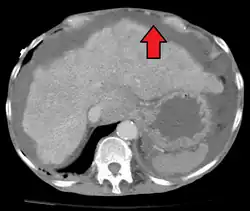

| Diagnostic method | Physical exam, ultrasound, CT scan[3] |

Ultrasound investigation is often done before attempts to remove fluid from the abdomen. This may reveal the size and shape of the abdominal organs, and Doppler studies may show the direction of flow in the portal vein, as well as detecting Budd–Chiari syndrome (thrombosis of the hepatic vein) and portal vein thrombosis. The sonographer also can estimate the amount of ascitic fluid, and difficult-to-drain ascites may be drained under ultrasound guidance. An abdominal CT scan is more accurate than a sonogram to reveal abdominal organ structure and morphology.[13]

- Grade 1: mild, only visible on ultrasound and CT